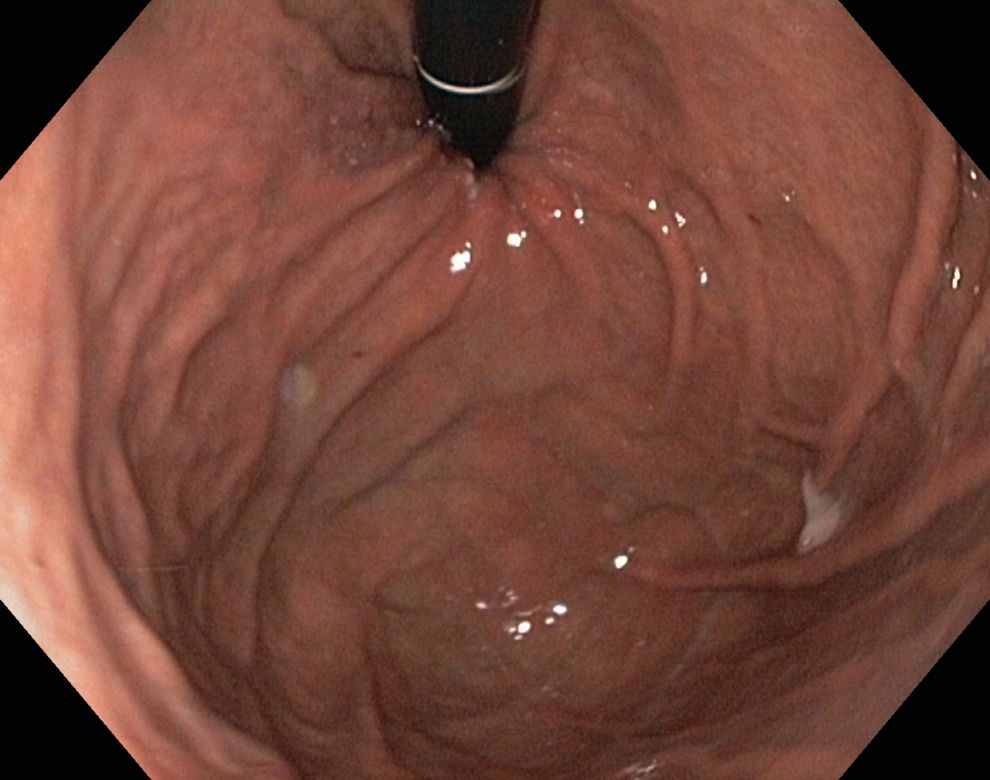

Die Untersuchung erfolgt mit einem so genannten Koloskop, einem steuerbaren, flexiblen Schlauch, der an ein Videosystem angeschlossen ist. Das Gerät wird vom Arzt vom After aus durch den Dickdarm geschoben. Zur besseren Sicht wird der Darm mit eingebrachter Luft oder Wasser sanft entfaltet.

Bei Bedarf können außerdem über einen Instrumentierkanal im Koloskop Gewebeproben (Biopsien) entnommen werden oder therapeutische Maßnahmen, wie Entfernung vom Darmpolypen, durchgeführt werden.

Dies ist nicht schmerzhaft, allerdings kann die Spiegelung selbst, besonders durch das Einblasen von Luft, als unangenehm empfunden werden. Daher empfehlen wir die Gabe eines schläfrig machenden Medikaments und eines Schmerzmittels, so dass die gesamte Untersuchung nicht wahrgenommen wird.